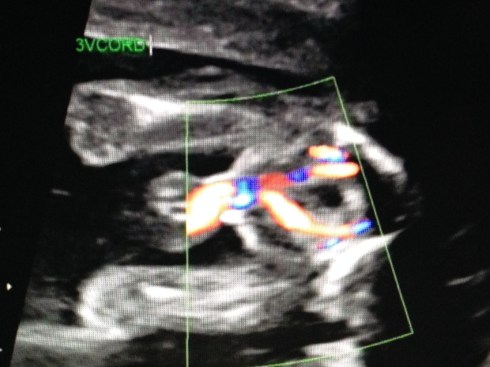

The ultrasound was performed on Friday, March 21, 2014 (at 19 weeks + 4 days). Our boy appeared healthy in all ways and weighed about 10 oz. His growth measurements were between 43% and 62% for his gestational age, and the heart rate was 147 bpm. The placenta is posterior and without previa. My cervix is long. Excellent!

We received a DVD of the scan. I took this short video clip with my phone, that shows baby’s face: moving his jaw, yawning, moving his tongue, and even smiling. You can also see his forearm in front of his face. Watch it again and look for the heart beating. Precious!!

I took these images by pausing the DVD and taking screen shots: